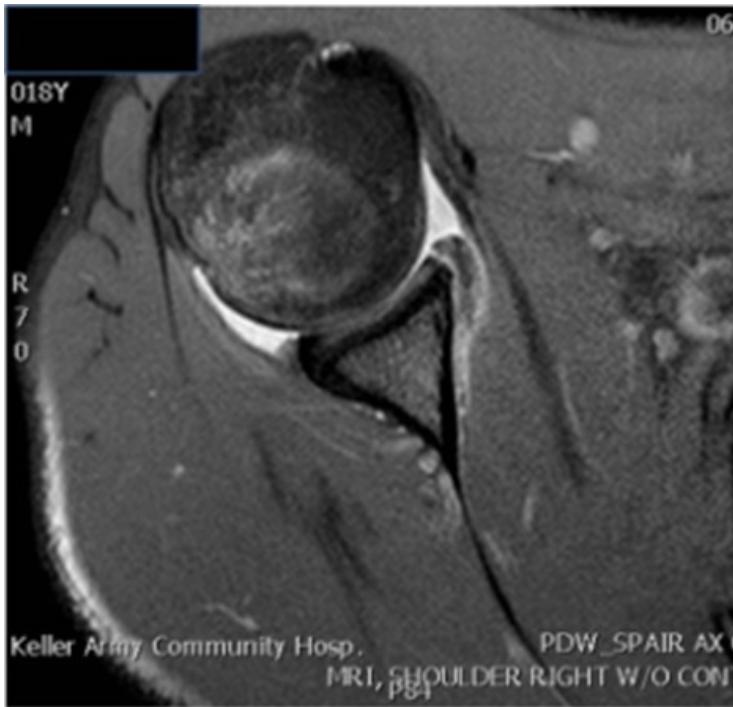

Case: Adhesive Capsulitis (Frozen Shoulder)

Clinical Scenario

- Patient: 55-year-old male, diabetic

- Complaint: Pain and restriction of shoulder movement

Physical Examination Findings:

Assessment Questions

Q1: Describe the physical finding?

- The patient is unable to raise his right hand above his head

Q2: What is your differential diagnosis?

- Adhesive capsulitis (Frozen Shoulder) - Primary diagnosis

- Acromioclavicular arthritis

Q3: What is the treatment for such a case?

- Steroid injection

- Physiotherapy

- Arthroscopic release